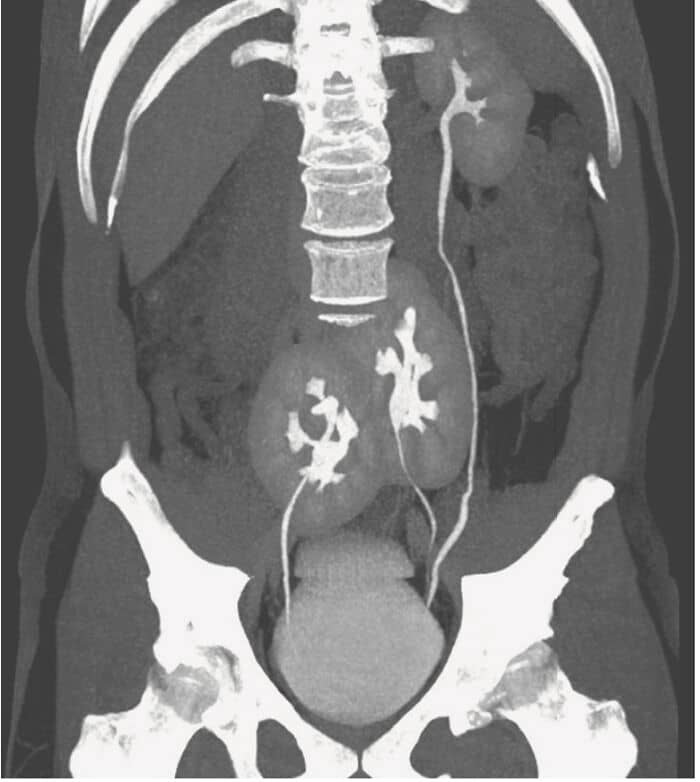

#50 Three Kidneys Discovered In A Man! – Medical Case

#51 Specialist Dentist Said I Had Some Of The Longest Teeth He’s Ever Removed